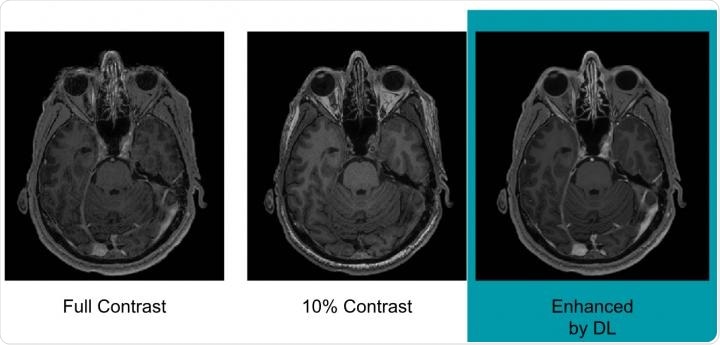

Example of full-dose, 10 percent low-dose and algorithm-enhanced low-dose. Credit: Radiological Society of North America.

Pre-contrast scans carried out before any contrast had been administered were referred to as zero-dose scans; those that used 10% of the standard gadolinium dose were referred to as low-dose scans and those that used 100% of the standard dose were referred to as full-dose scans.

Gong and colleagues report that the algorithm was able to discern between all three sets of scans.

The results showed that the image quality did not differ significantly between the three scan sets and also indicated that the equivalent of full-dose scans could be generated without using any gadolinium at all.